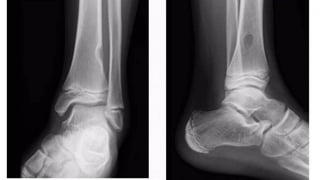

Septations

• Coarse and thick - chondromyxoid fibroma.

• Delicate and thin - Gaint cell tumor

• Horizontal - ABC

• Lobulated - NOF

• Striated,radiating - hemangioma.